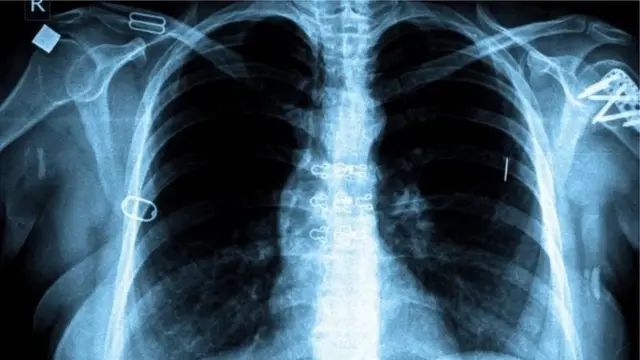

Cette maladie pulmonaire est provoquée par le bacille tuberculeux - appelé scientifiquement mycobacterium tuberculosis - qui touche le plus souvent les poumons.